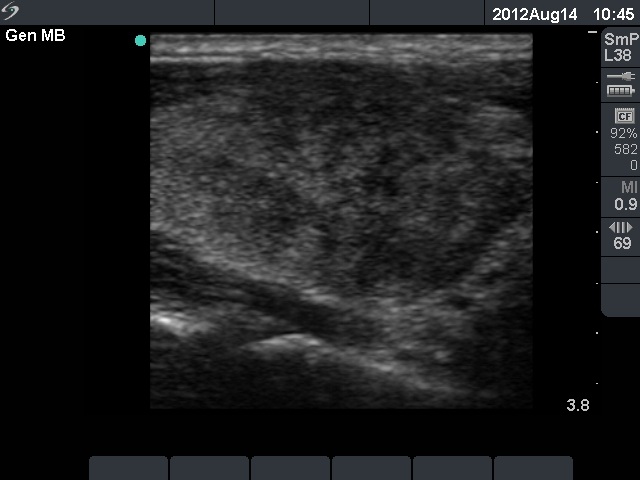

First examination (1st and 2nd rows of images):

Clinical presentation: a 45-year-old woman was referred with typical complaints of subacute thyroiditis: fever, pain in the region of the left thyroid lasting for 4 weeks.

Palpation: the left thyroid was hard and painful, while the right thyroid was moderately firm and not tender.

Functional state: moderate degree of hyperthyroidism with TSH-level 0.001 mIU/L, FT4 35.1 pM/L. ESR 70 mm/H, CRP 21.7 mg/L.

Ultrasonography: there were multiple hypoechogenic areas with blurred borders within echonormal background in the left thyroid. The vascularization was decreased. The right thyroid was intact and had normal vascularization.

Cytological diagnosis: subacute, granulomatous de Quervain's thyroiditis.

Suggestion: steroid therapy. The complaints of the patient suddenly stopped within 24 hours after the steroid intake.